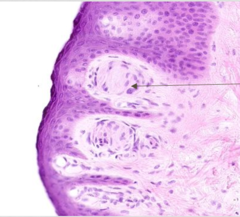

epidermal ridge

Front

what part of the epidermis is this?

Back